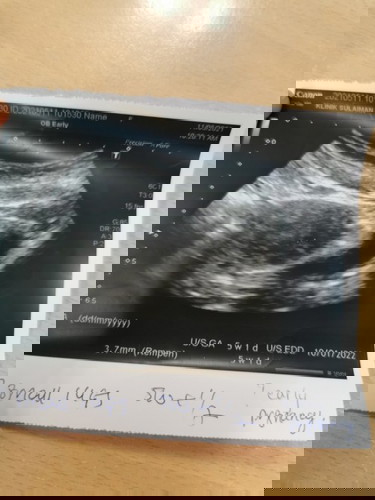

11.05.2021 [4 pagi] : CBD Positif 1-2 (UPT strip sangat-sangat samar) Jumpe doc scan ada kantung, kandungan masih awal lagi, doc bg ubat DUPHASTON utk kuat kn rahim, saya bleeding 2 hari & dah stop bleeding. 14.05.2021 [7 mlm] : CBD result NOT PREGNANT, UPT masih samar lagi. Adakah saya mengandung???? #ingintahu #bantusharing #firstbaby #seriusnanya